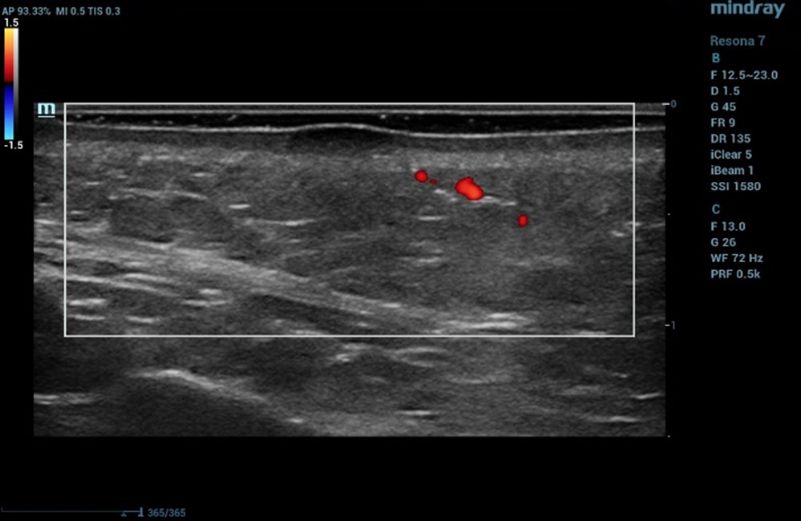

Ultrasound examination of the nevus was performed on the Resona 7 ultrasound machine (Mindray, China) using the high frequency linear transducer L20-5U (max frequency 23 MHz). When the transducer was placed in the projection of the visible nevus of the right zygomatic region of the face, the derma was locally thickened to 2.4 mm due to a hypoechogenic mass located under the epidermis and slightly elevated, spreading in depth to all layers of the dermis with clear rough boundary of heterogeneous echogenicity, without hyperechogenic sports, giving a weak acoustic darkening of the echo signal (Figure 2). Blood flow is not registered inside the nevus in the Color Doppler mode (Figure 3).

Ultrasound examination of the nevus in B mode

Figure 2. Ultrasound examination of the nevus in B mode

Such ultrasound signs are characteristic of compound nevus [2]. A pronounced subcutaneous low-echo band (SLEB) attracts attention (0.9 mm – 50% of the total thickness of the dermis – 1.7 mm), which is the ultrasound sign of facial skin photodamage [3].